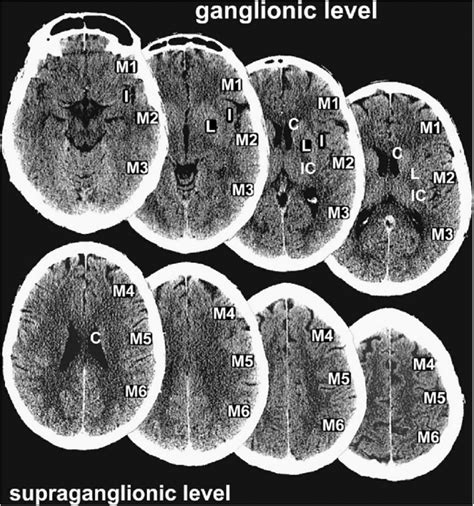

ASPECTS шкала

ASPECTS шкала Шкала ASPECTS (Alberta Stroke Program Early CT score – програма Alberta для оцінки ранніх КТ змін при інсульті) – це... Читати далі